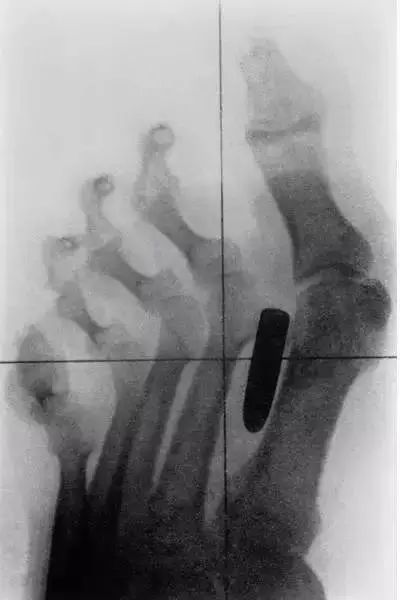

14、这是一个士兵足部的X光片,显示了他的枪伤。*弹子**没有损伤任何骨骼,但由于长期穿着军靴和步行,这颗*弹子**改变了骨骼的形状。